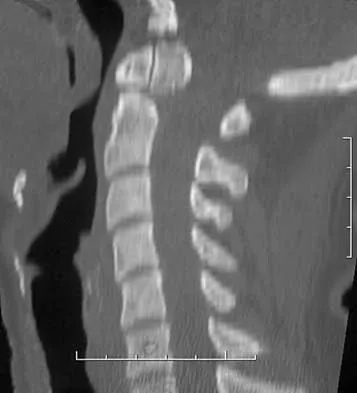

Following a fall from a height of 5 feet, a patient reports pain along the lateral border of the foot. The CT scan shown in Figure 54 indicates what pathology?

Anatomy Board Review 2008: High-Yield MCQs (Set 4) - Figure 22

Explanation

The CT scan reveals an avulsion of the dorsal beak of the anterior process of the calcaneus. This common fracture is an avulsion of the origin of the bifurcate ligament, which runs from the anterior calcaneal process to both the cuboid and the lateral aspect of the navicular. An inversion mechanism is common, and the fracture is often missed in evaluation for a suspected ankle sprain. MRI may be useful in the diagnosis of these occult injuries, and suspicion should be present when tenderness exists over the superior portion of the anterior process of the calcaneus.